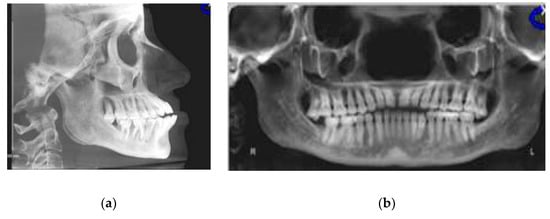

2.1. Case Presentation

3.2.1. Cephalometric Radiographs and Analysis

3.2.2. Panoramic and Sagittal Screen Radiographs